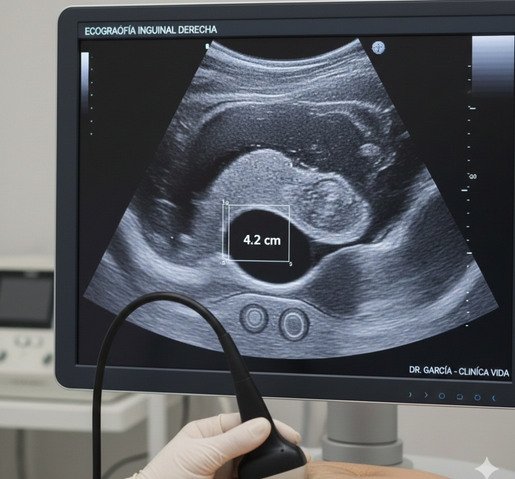

Ecografía Inguinal

La ecografía inguinal es un estudio no invasivo que permite evaluar la región inguinal, analizando músculos, tejidos blandos, ganglios y estructuras adyacentes. Es una herramienta fundamental para la detección y evaluación de hernias inguinales, adenopatías, colecciones, masas o procesos inflamatorios.

Se trata de un estudio seguro, indoloro y de rápida realización, indicado tanto ante la presencia de dolor, aumento de volumen o molestias en la región inguinal, como en el control y seguimiento de patologías conocidas.